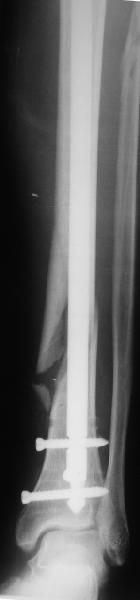

Взвесив все <<за>> и <<против>>, мы приняли решение и выполнили реостеостинтез: выбили гвоздь до линии перелома, провели отклоняющую

спицу, забили обратно гвоздь и заблокировали внизу 3-мя винтами, вверху одним. Вся операция заняла меньше часа. Сегодня пациент ушел от нас домой с полной нагрузкой на ногу.